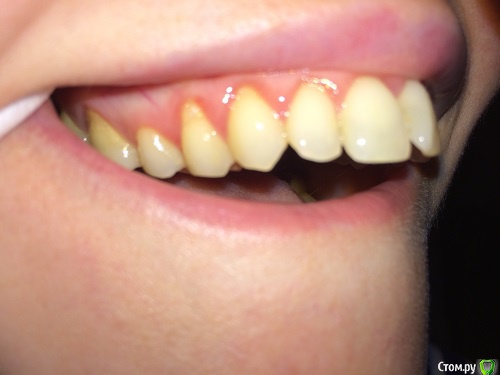

lalafa Опубликовано 16 августа, 2017 Поделиться Опубликовано 16 августа, 2017 (изменено) Здравствуйте, помогите, пожалуйста, советами.Мне 29 лет. Хронические заболевания - гранулезный фарингит, гастрит, ГЭРБ, сколиоз. У меня генерализованная рецессия десны, катаральный гингивит, пародонтальных карманов нет. Рекомендовано ортодонтическое лечение. НО ортодонты предупредили, что велика вероятность продолжения рецессии десны во время лечения и ухудшения ситуации. Посетила 2 пародонтологов, мнения противоположные. Один рекомендует операцию по закрытию рецессии методом пересадки трансплантата с неба. Хочет оперировать до ортодонт лечения самые проблемные зубы - клыки на нижней челюсти и 4ку. Мотив - утолщить десну, чтобы она выдержала брекеты и не рецессировала еще больше.Другой пародонтолог говорит, что так как именно эти зубы "не стоят в зубной дуге" (цитата врача) трансплантат с неба не приживется и результата не будет. Советует делать операцию после снятия брекетов на прямые зубы.Вопросы:1) Насколько в принципе опасно при такой рецессии проводить ортодонтическое лечение? зубы могут расшатываться и выпасть в процессе лечения?2) Закрывать рецессию до брекетов или после? Действительно, на таких вывернутых зубах не приживается трансплантат?3) Постоянно мучаюсь с катаральным гингивитом. Прохожу Проф чистку раз в 6 месяцев, но без толку. за чистотой слежу и самостоятельно, но скученные зубные ряды все равно провоцируют гингивит. Можно надеяться, что после брекетов гингивит вылечится? Изменено 16 августа, 2017 пользователем lalafa Ссылка на комментарий

lalafa Опубликовано 17 августа, 2017 Автор Поделиться Опубликовано 17 августа, 2017 Про гигиену чищу зубы как показал стоматолог, по схеме.Нитью больно пользоваться, потому что сильная скученность.После проф чистки гингивит все равно есть, просто десны не кровоточат, но они красные и припухшие. фото сделаны после недели применения ополаскивателя, от которого сильно желтеют зубы, поэтому такой вид, как будто проблемы с гигиеной.Скажите. пожалуйста, на снимке есть признаки пародонтоза? Ссылка на комментарий

Art 7 Опубликовано 17 августа, 2017 Поделиться Опубликовано 17 августа, 2017 ополоскиватель не окрашивает зубы, он окрашивает налёт. пластику до брекетов, вы не первая со скученностью, есть и сложнее ситуации когда пациенты справляются. породонтоза у вас нет Ссылка на комментарий